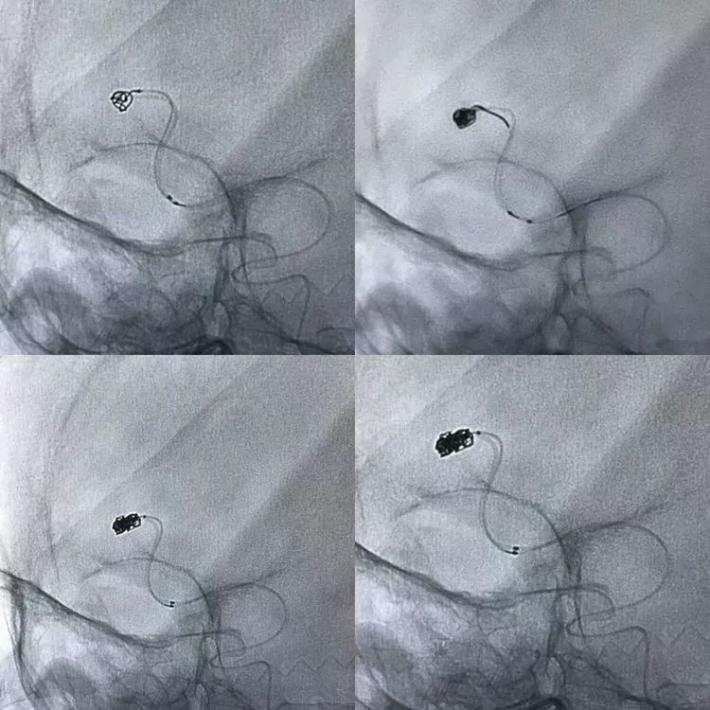

手术过程

全麻,左侧颈内动脉入路,引导微导管通过前交通,步步为营,慢慢到达瘘口。现在解剖结构很清楚了,供血动脉来源于右侧大脑前动脉A2段,在额极动脉和胼缘动脉之间发出,引流于下矢状窦。

看到这个手推造影,心情大好啊,没有想象的复杂了,瘘的流量并不高。单纯弹簧圈栓塞应该就可以了,不用担心栓塞材料逃逸了。

师父说: 把稳点!

心有灵犀,一点即通!好,再来根微导管,两根导管同时到位。

双导管耍的溜溜的,依次填塞解脱弹簧圈,至瘘不显影。